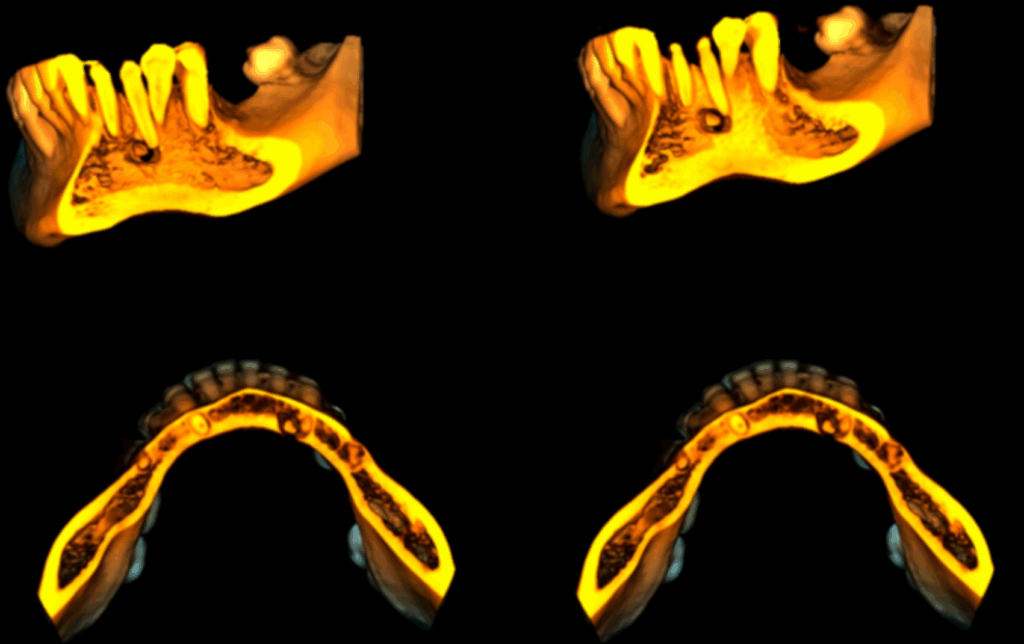

En las reconstrucciones 3D se representa de manera didáctica Lesión Fibroósea. (Figura 4).

RECONSTRUCCIÓN 3D

Conclusión: Lesión Fibroósea